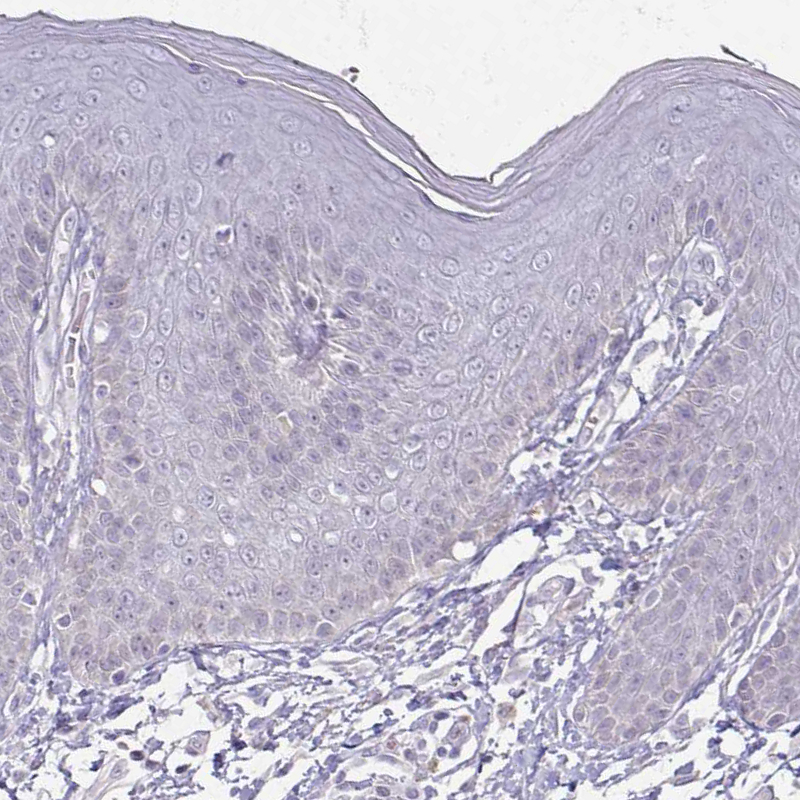

Immunohistochemical staining of human urinary bladder shows moderate positivity in plasma in blood vessels.